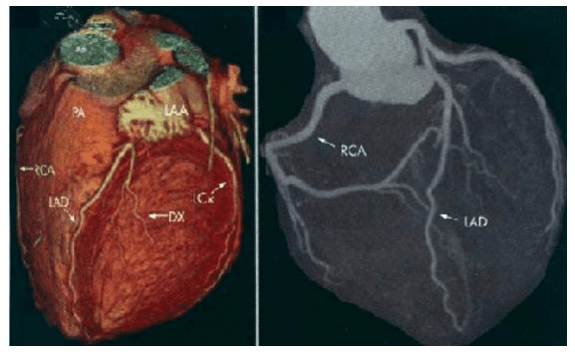

CT Angiography Other Than Coronary

A coronary CT angiogram is different from a standard coronary angiogram. In the traditional procedure (non- CT angiogram), a flexible tube (catheter) is threaded through your groin or arm to your heart or coronary arteries